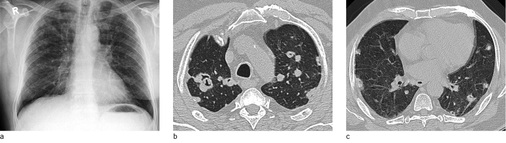

In der Computertomographie zeigt die chronische unkomplizierte Form der Silikose überwiegend scharf berandete zum Teil auch verkalkte Noduli (Chong et al. 2006; Cox et al. 2014). Charakteristisch ist eine perilymphatische Verteilung der Knötchen. Diese liegen sowohl im Lungenmantel, hier radiologisch von der Pleura nicht zu trennen, als auch im Parenchym, entsprechend der Ablagerung des inhalierten Staubs, meist in der Umgebung der respiratorischen Bronchiolen. Auch in der Pleura visceralis selbst können durch den Abtransport von Quarzstaub über die pleuralen Lymphbahnen silikotische Noduli im Verlauf der Lymphbahnen entstehen. Da bei Mischstaubablagerungen häufig geringfügig fibrös-entzündliche Reaktionen ablaufen (Müller 1983), kommt es zu Einziehungen der Pleura visceralis, dadurch wird das silikotische Knötchen scheinbar in das Lungenparenchym eingezogen (Ulmer u. Reichel 1976). Bei ungünstiger Dokumentation in der Computertomographie, d.h. Darstellung nicht in allen drei Raumebenen, können peripher gelegene silikotische Noduli bildmorphologisch mit asbestassoziierten parietalen Verdickungen der Pleura verwechselt werden. Zu dieser Missinterpretation tragen auch die im angloamerikanischen Sprachgebrauch üblichen und teilweise in den deutschen Sprachgebrauch übernommenen Bezeichnungen „Pseudoplaques“ oder „subpleural pearls“ für diese Lokalisation silikotischer Noduli bei (  Abb. 3a,b ).

Silikotische Noduli sind überwiegend in den Oberlappen und den kranialen Anteilen der Unterlappen lokalisiert. Sie finden sich dominant dorsal der Trachealebene. Die Anzahl der Herde nimmt üblicherweise von kranial nach kaudal ab. Beginnende Koaleszenzen der silikotischen Noduli sind in der Computertomographie deutlicher als anhand der Übersichtsaufnahmen abzugrenzen. Dominiert der Staubanteil mit geringer fibrogener Wirkung, zeigen sich der Computertomographie vor allem bronchioloalveoläre Verdickungen und unscharfe zentrilobuläre Knötchen sowie ein Lungenemphysem.